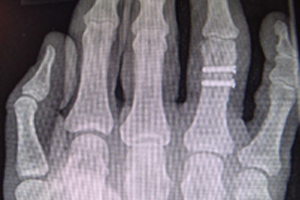

Diagnose: Mehrfragmentfraktur am Ringfingergrundglied rechts (s. Abb. 1)

Therapie: Osteosynthese mit 2 Schrauben (s. Abb. 2)

Die Klägerin war gestürzt und hatte sich die rechte Hand verletzt. Die ärztliche Erstversorgung erfolgte am Unfalltag in der beklagten Klinik. In den Röntgenaufnahmen der rechten Hand wurde eine Mehrfragmentfraktur am Ringfingergrundglied diagnostiziert, die 10 Tage später offen reponiert und mit 2 Schrauben osteosynthetisch stabilisiert wurde.